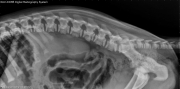

Today’s case is an 8-week-old male German Shepherd with acute onset of non-ambulatory paraparesis. What are your findings?

R LAT Spine

There is radiolucency, collapse, and kyphosis associated with the T1 and T2 vertebral bodies. The ventral border of the L5 vertebral body is mildly asymmetric, and the caudal physis is widened and irregular. No abnormalities are noted in the remainder of the spine.

Subluxation at T1-2 with vertebral collapse. Physeal displacement and vertebral body sclerosis at L5.

• Hematogenous infectious inflammatory disease

• Previous trauma

• Congenital malformation

An MRI was performed, revealing severe spinal cord compression at T1-2. The findings at L5 were confirmed; however, no spinal cord compression was present.